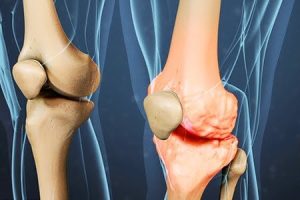

از خواص سیاه دانه (Nigella sativa) برای درمان بیماریهای مختلف مانند التهابات مفصلی (Joint inflammations)، آسم (Asthma)، آلرژیها (allergy)، عفونتهای قارچی، آرتروز (Arthritis)، دیابت (diabetes) و بیماریهای قلبی-عروقی استفاده میشود. سیاه دانه دارای ویژگیهای طبیعی و دارویی متعددی است. این دانه شامل عناصری همچون اسیدهای چرب اشباع نشده، چربیهای غیراشباع چندگانه مانند امگا-۶ و امگا-۹ و عناصر معدنی مختلف مانند کلسیم (Calcium)، آهن (iron)، منگنز (Manganese) و روی (zinc) است. همچنین، این گیاه دارای ترکیباتی است که خاصیت ضدباکتریایی، ضدویروسی و ضدقارچی دارند.

- ضد التهاب: سیاه دانه خواص ضد التهابی دارد و میتواند در کاهش التهابات داخلی و خارجی بدن موثر باشد. این خاصیت میتواند به درمان بیماریهای التهابی مانند آرتروز و التهابات روده کمک کند.

- ضد التهاب: این ترکیب میتواند در درمان بیماریهای التهابی مانند التهاب مفصل، آسم و التهابات روده موثر باشد.

- اثر ضد التهابی: سیاه دانه دارای خواص ضد التهابی است و به کاهش التهابهای داخلی بدن کمک میکند. این خاصیت میتواند در تسکین علائم التهابی مانند درد و التهابات مفصلی موثر باشد.